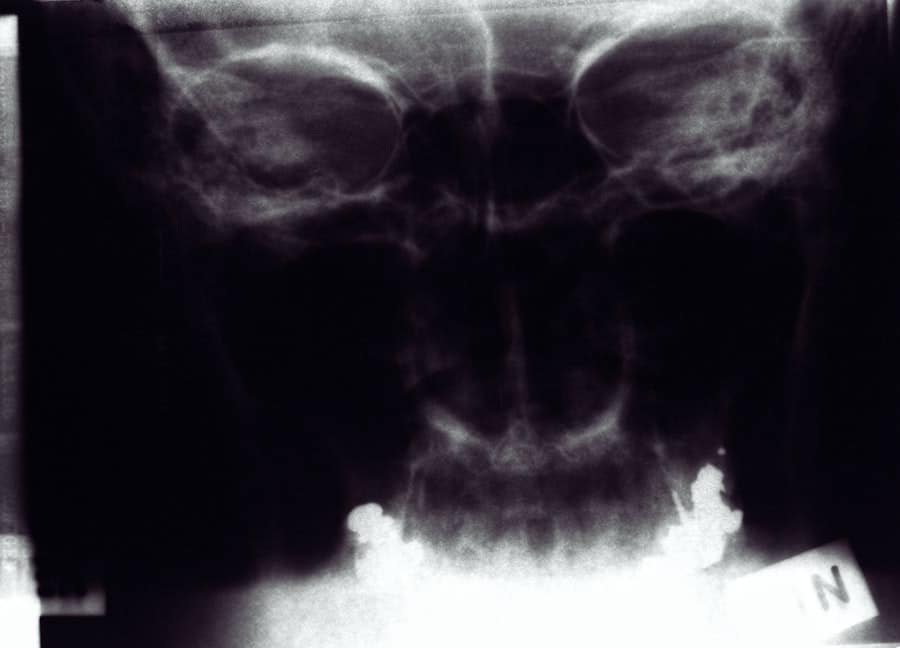

Several factors can significantly influence the overall cost of rhinoplasty. One of the primary considerations is the complexity of your specific case. If you require extensive reshaping or correction of structural issues, such as a deviated septum, you may find that the costs increase accordingly.